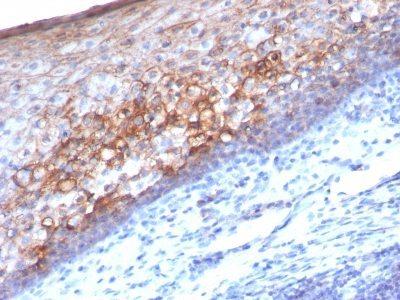

Positive Control

A-375, HUV-EC or HeLa Cells. Tonsil or Melanoma.

Melanoma

Higher concentration may be required for direct detection using primary antibody conjugates than for indirect detection with secondary antibody|Immunohistology (formalin)|Staining of formalin-fixed tissues requires boiling tissue sections in 10 mM Tris with 1 mM EDTA, pH 9.0, for 10-20 min followed by cooling at RT for 20 minutes|Flow Cytometry 0.5-1 ug/million cells/0.1 mL|Immunofluorescence 0.5-1.0 ug/mL|Optimal dilution for a specific application should be determined by user